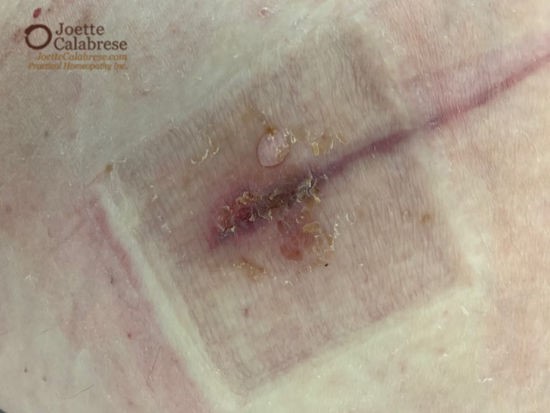

Wie schlimm war das Ganze nun wirklich? Ich würde sagen: „Wenn Sie zart besaitet sind, sollten Sie nicht mehr weiter scrollen“.

Meine Mitarbeiterin brachte den Vergleich mit einer Schusswunde ins Spiel (sie hat zwar noch keine Echte gesehen, dafür aber ganz viele alte Western!). Die Wunde war knapp zwei Zentimeter tief und sehr stark entzündet.

Wie Sie anhand des Fotos erkennen können, hatte sich die Wunde entzündet und die Infektion war zu einem ernstzunehmenden Problem geworden. Zum Glück verordnete dieser etwas „altmodische“ Arzt nicht gleich ein systemisches Antibiotikum. So konnte meine Mitarbeiterin auf das rettende Banerji-Protokoll zurückgreifen:

Das folgende Foto wurde nur drei Wochen später aufgenommen. Die Wundheilung haben wir Hyper/Ars zu verdanken – und einem „altmodischen“ Chirurgen, der wusste, wie man auch in der Not eine Wunde richtig verarztet: regelmäßiger Verbandswechsel für zwei Wochen und anschließend Leukoplast.